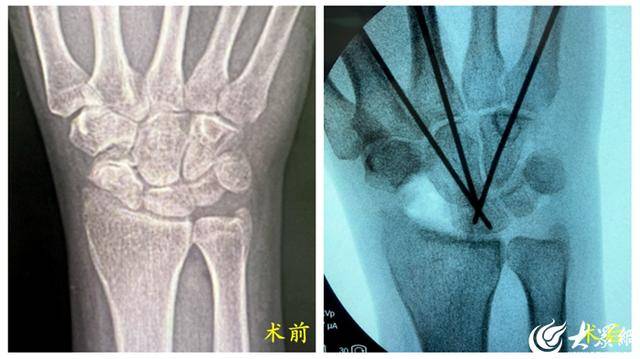

43岁的王先生(化名)20多年前因腕舟骨骨折未规范治疗,长期遭受钻心疼痛和手腕活动受限的折磨。简单地拧毛巾、提重物,对他而言都是难以完成的奢望,严重时甚至影响睡眠质量。经影像学检查进一步确诊,王先生不仅存在陈旧性骨折不愈合的问题,还伴有舟骨异常旋前、月骨异常背伸的情况,医学上称之为“腕关节背侧镶嵌节段不稳定”——这是腕部损伤中较为严重且少见的类型。此前,针对此类复杂病症,传统开放手术不仅创伤大,术后还容易对患者腕关节功能造成显著影响,患者往往面临“术后恢复慢、功能难回归”的困境。

为给王先生制定最优治疗方案,手外科、足踝外科主任张诚牵头组织团队进行了多次术前讨论,围绕患者病情特点、手术风险控制、术后功能恢复等关键问题展开细致分析。同时,为确保手术方案的科学性与安全性,团队还特别联系山东大学齐鲁医院朱磊教授进行远程会诊,最终确定采用“腕关节镜下腕舟骨切除+头月融合术”这一微创方案。手术由手外科、足踝外科主任医师张诚、副主任医师单连良、主治医师孙平共同协作完成,术中通过腕关节镜精准探查,清晰可见患者桡舟关节面磨损严重、舟骨陈旧性骨折不愈合的具体情况,随后顺利完成腕舟骨切除与头月融合操作。术中C臂透视结果显示,舟骨切除彻底,内固定位置精准理想,最大程度为患者保留了腕关节功能。目前,王先生已顺利出院休养。